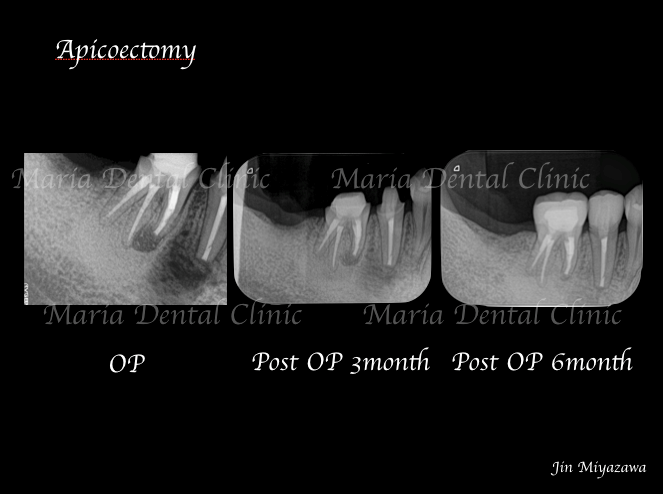

歯根端切除術症例1|術後6ヶ月で徐々に根尖透過像が縮小

目白マリア歯科の症例ページで7月にご紹介させていただいた歯根端切除術の経過

【症例】抜歯を宣告された歯を外科的根管治療「歯根端切除術」で保存

のレントゲン写真を例にして見ていだければわかるように、根尖病変を除去した後6ヶ月をかけて徐々に根尖透過像(※)の縮小が確認できます。歯肉は比較的早い治癒を確認できますが、骨透過像の治癒は時間をかけてゆっくりと縮小し、半年後にはほぼ透過像の確認はできない状態まで良好な治癒を示しています。

この症例のように、定期的なレントゲン写真を撮影することで予後の変化を確実に診断できるようになります。